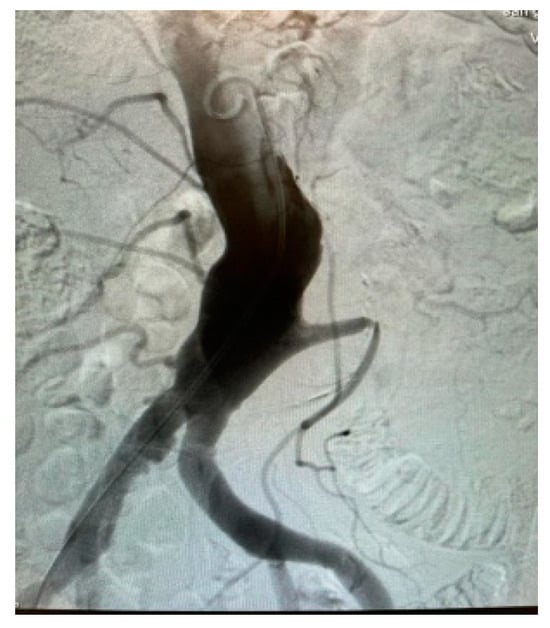

Appendix A.1. Clinical Case 1: Right Renal Visceral Arteriovenous Malformation